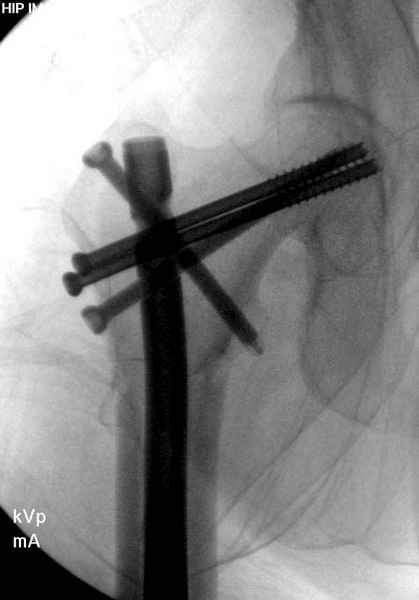

Профилактику дальнейшего раскола неполного перелома шейки провели тремя канюлированными шурупами.

Наверное речь идет насчет parallel guide из набора. Применяем по возможности всегда, но,

как видно на снимке, не всегда получается

паралельно.

Такие несмещенные переломы обычно для молодых резидентов, и бывают технические неточности, но в этом случае посчитали фиксацию адекватной.